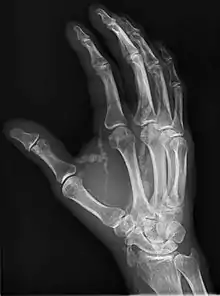

| Hand radiograph showing tumoral calcinosis, PA radiograph of the right hand showing tumoral calcinosis-like metastatic calcification in a patient on dialysis. Dialysis alters calcium phosphate product (>70). Idiopathic tumoral calcinosis is autosomal dominant and is not associated with dialysis. Note the premature arterial calcification which is a clue that this is a renal patient. Vascular calcification contributes to an increase in morbidity. |

Tumoral calcinosis is a rare condition in which there is calcium deposition in the soft tissue in periarticular location, around joints, outside the joint capsule.[1] They are frequently (0.5–3%) seen in patients undergoing renal dialysis. Clinically also known as hyperphosphatemic familial tumoral calcinosis (HFTC), is often caused by genetic mutations in genes that regulate phosphate physiology in the body (leading to too much phosphate (hyperphosphatemia)). Best described genes that harbour mutations in humans are FGF-23,[2] Klotho (KL),[3] or GALNT3.[4] A zebrafish animal model with reduced GALNT3 expression also showed HFTC-like phenotype,[5] indicating an evolutionary conserved mechanism that is involved in developing tumoral calcinosis.